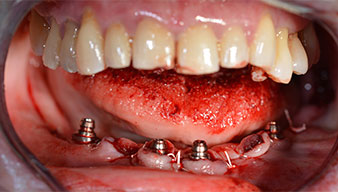

Die nächste programmierte Einstellung ist bereits die Implantateinbringung. Die Implantate werden in unserem Hause standardmäßig mit einer Kraft von 32Ncm inseriert (Abb. 12 und 13).

Die absolute Voraussetzung für die Sofortversorgung ist die hohe Primärstabilität. Um diese zu erfüllen, wurde in diesem Fall auf ein Gewindeschneiden verzichtet. Die hier verwendete Antriebseinheit Implantmed von W&H besitzt hierfür einen eigenen Modus, der ebenfalls direkt anwählbar und für viele Indikationen unverzichtbar ist. Die letzten Umdrehungen bei der Implantateinbringung überschritten den Wert von 32Ncm und wurden manuell durchgeführt. Hierfür empfiehlt es sich, die Selbstschneidefunktion der Implantate auszunutzen und das Implantat mehrmals vorwärts und rückwärts zu drehen. So gelangt das Implantat schrittweise näher bis zur endgültigen Position, ohne zu starken Druck auf den Knochen auszuüben (Abb. 14).

Um die Divergenz der distalen Implantate auszugleichen, werden abgewinkelte Abutments (35 Grad) eingeschraubt, sodass die Austrittsprofile sämtlicher Implantate möglichst senkrecht zur Kauebene stehen. Dies ist Voraussetzung, um die provisorische und später auch die endgültige Versorgung okklusal verschrauben zu können (Abb. 15 und 16).